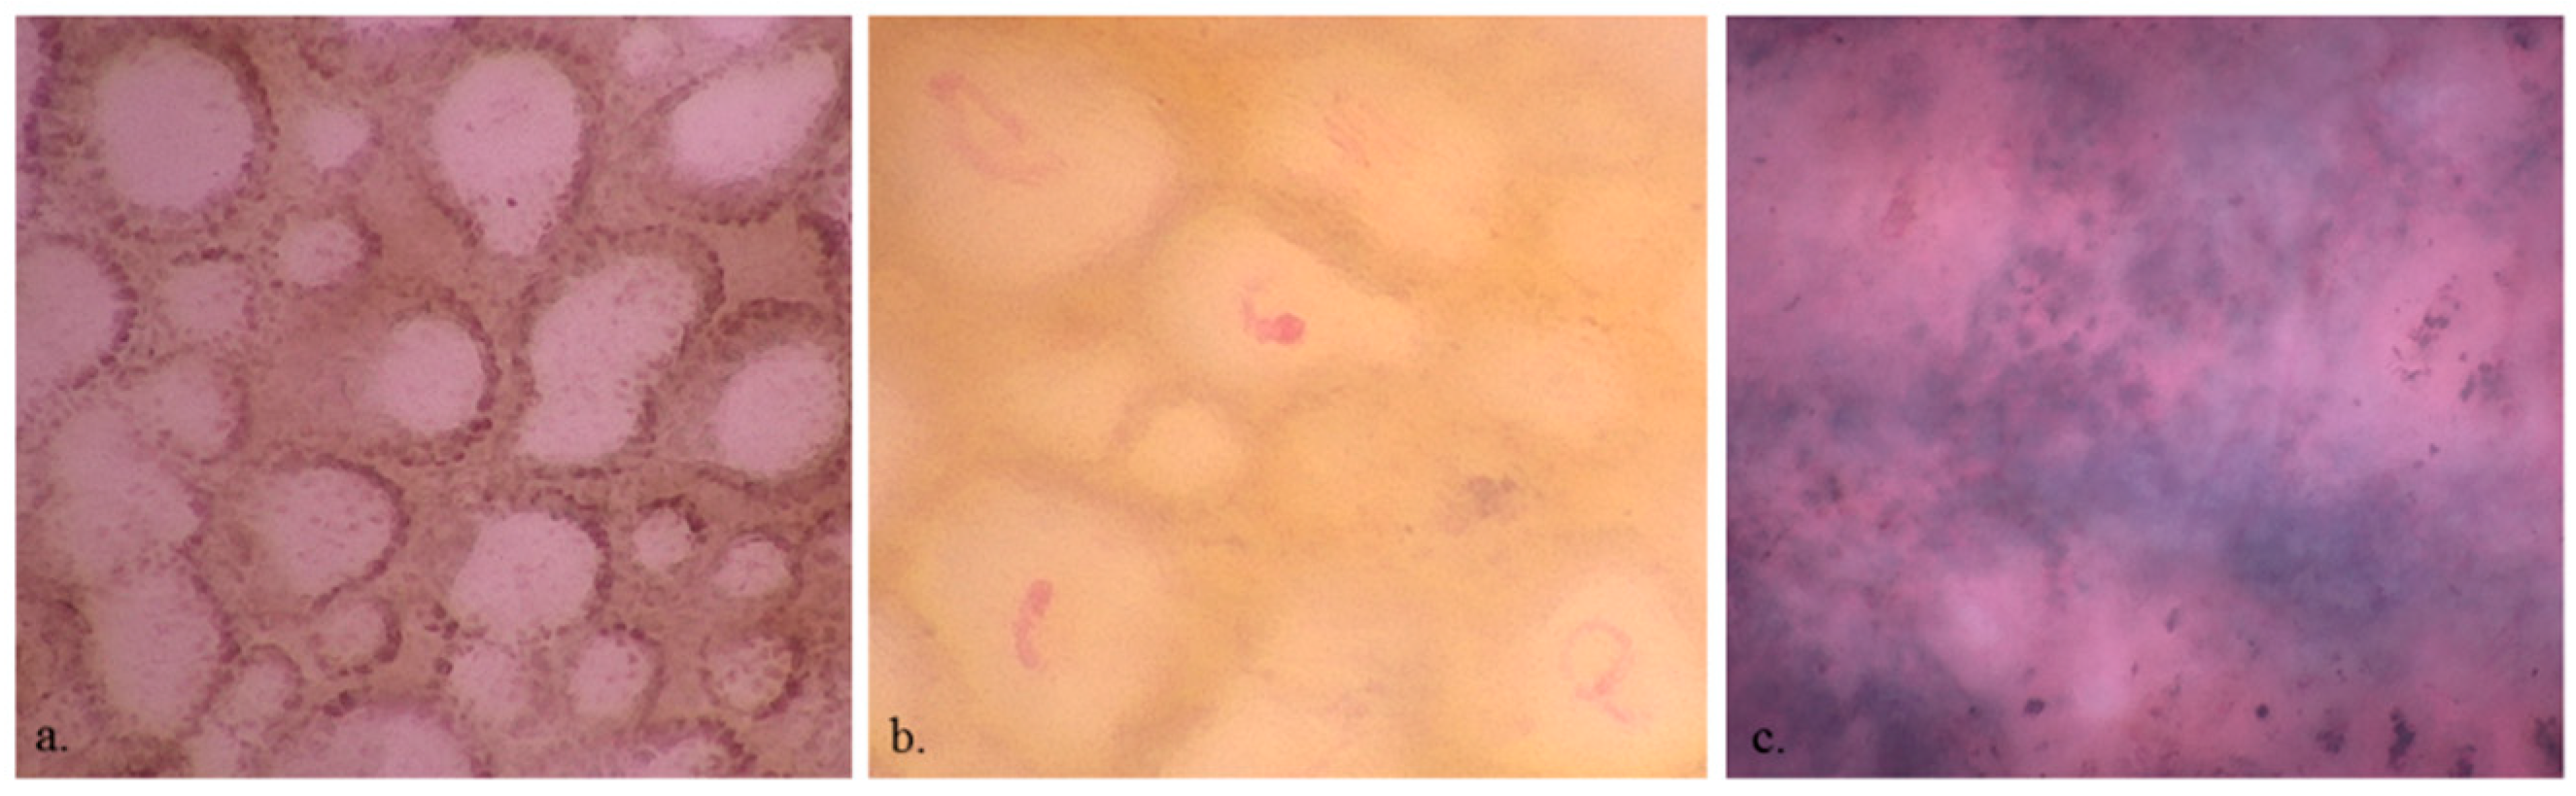

- Cinotti, E.; Tognetti, L.; Campoli, M.; Liso, F.; Cicigoi, A.; Cartocci, A.; Rossi, R.; Rubegni, P.; Perrot, J.L. Super-high magnification dermoscopy can aid the differential diagnosis between melanoma and atypical naevi. Clinical and experimental dermatology 2021, 46, 1216–1222. [Google Scholar] [CrossRef] [PubMed]